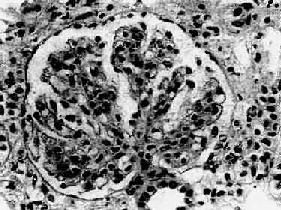

膜性腎小球腎炎(membranous glomerulonephritis)是臨床上以大量蛋白尿或腎病綜合徵為主要表現病理上以腎小球毛細血管基底膜均勻一致增厚,有瀰漫性上皮下免疫複合物沉積為特點,不伴有明顯細胞增生的獨立性疾病

本病為免疫複合物長期、緩慢沉積於上皮細胞下(又稱慢性免疫複合物沉積病)。一般不引起炎症細胞反應,而通過補體的終末成分C3b~C9是補體的攻膜系統,導致基底膜損傷。免疫螢光顯示有顆粒狀IgG、C3沉積於腎小球基底膜。Dixon等在動物實驗中,以每日2mg低劑量異性蛋白注入家兔產生慢性血清病,循環免疫複合物沉積導致膜性腎病。

本病的確診主要靠腎活檢病理學檢查。

成人以大量蛋白尿尤其是以腎病綜合徵為主要表現者,應疑及本病;確診靠腎病理學檢查。早期膜性腎小球腎炎應與輕微病變或局灶性腎小球硬化鑑別,有時在光鏡下不能區別,需電鏡檢查區別。